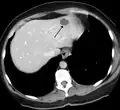

- A liver hemangioma as seen on CT

Infantile haemangiomas in the liver are found in 16% of all liver haemangiomas. Its sizes are usually less than 1 to 2 cm in diameter. It may show a "flash-filling" phenomenon in which there is the fast enhancement of the contrast material in the lesion instead of slow, centripetal, nodular filling of the lesions in usual hemangiomas. On CT and MRI, it shows rapid filling during arterial phase, with contrast retention in venous and delayed phases.[38]